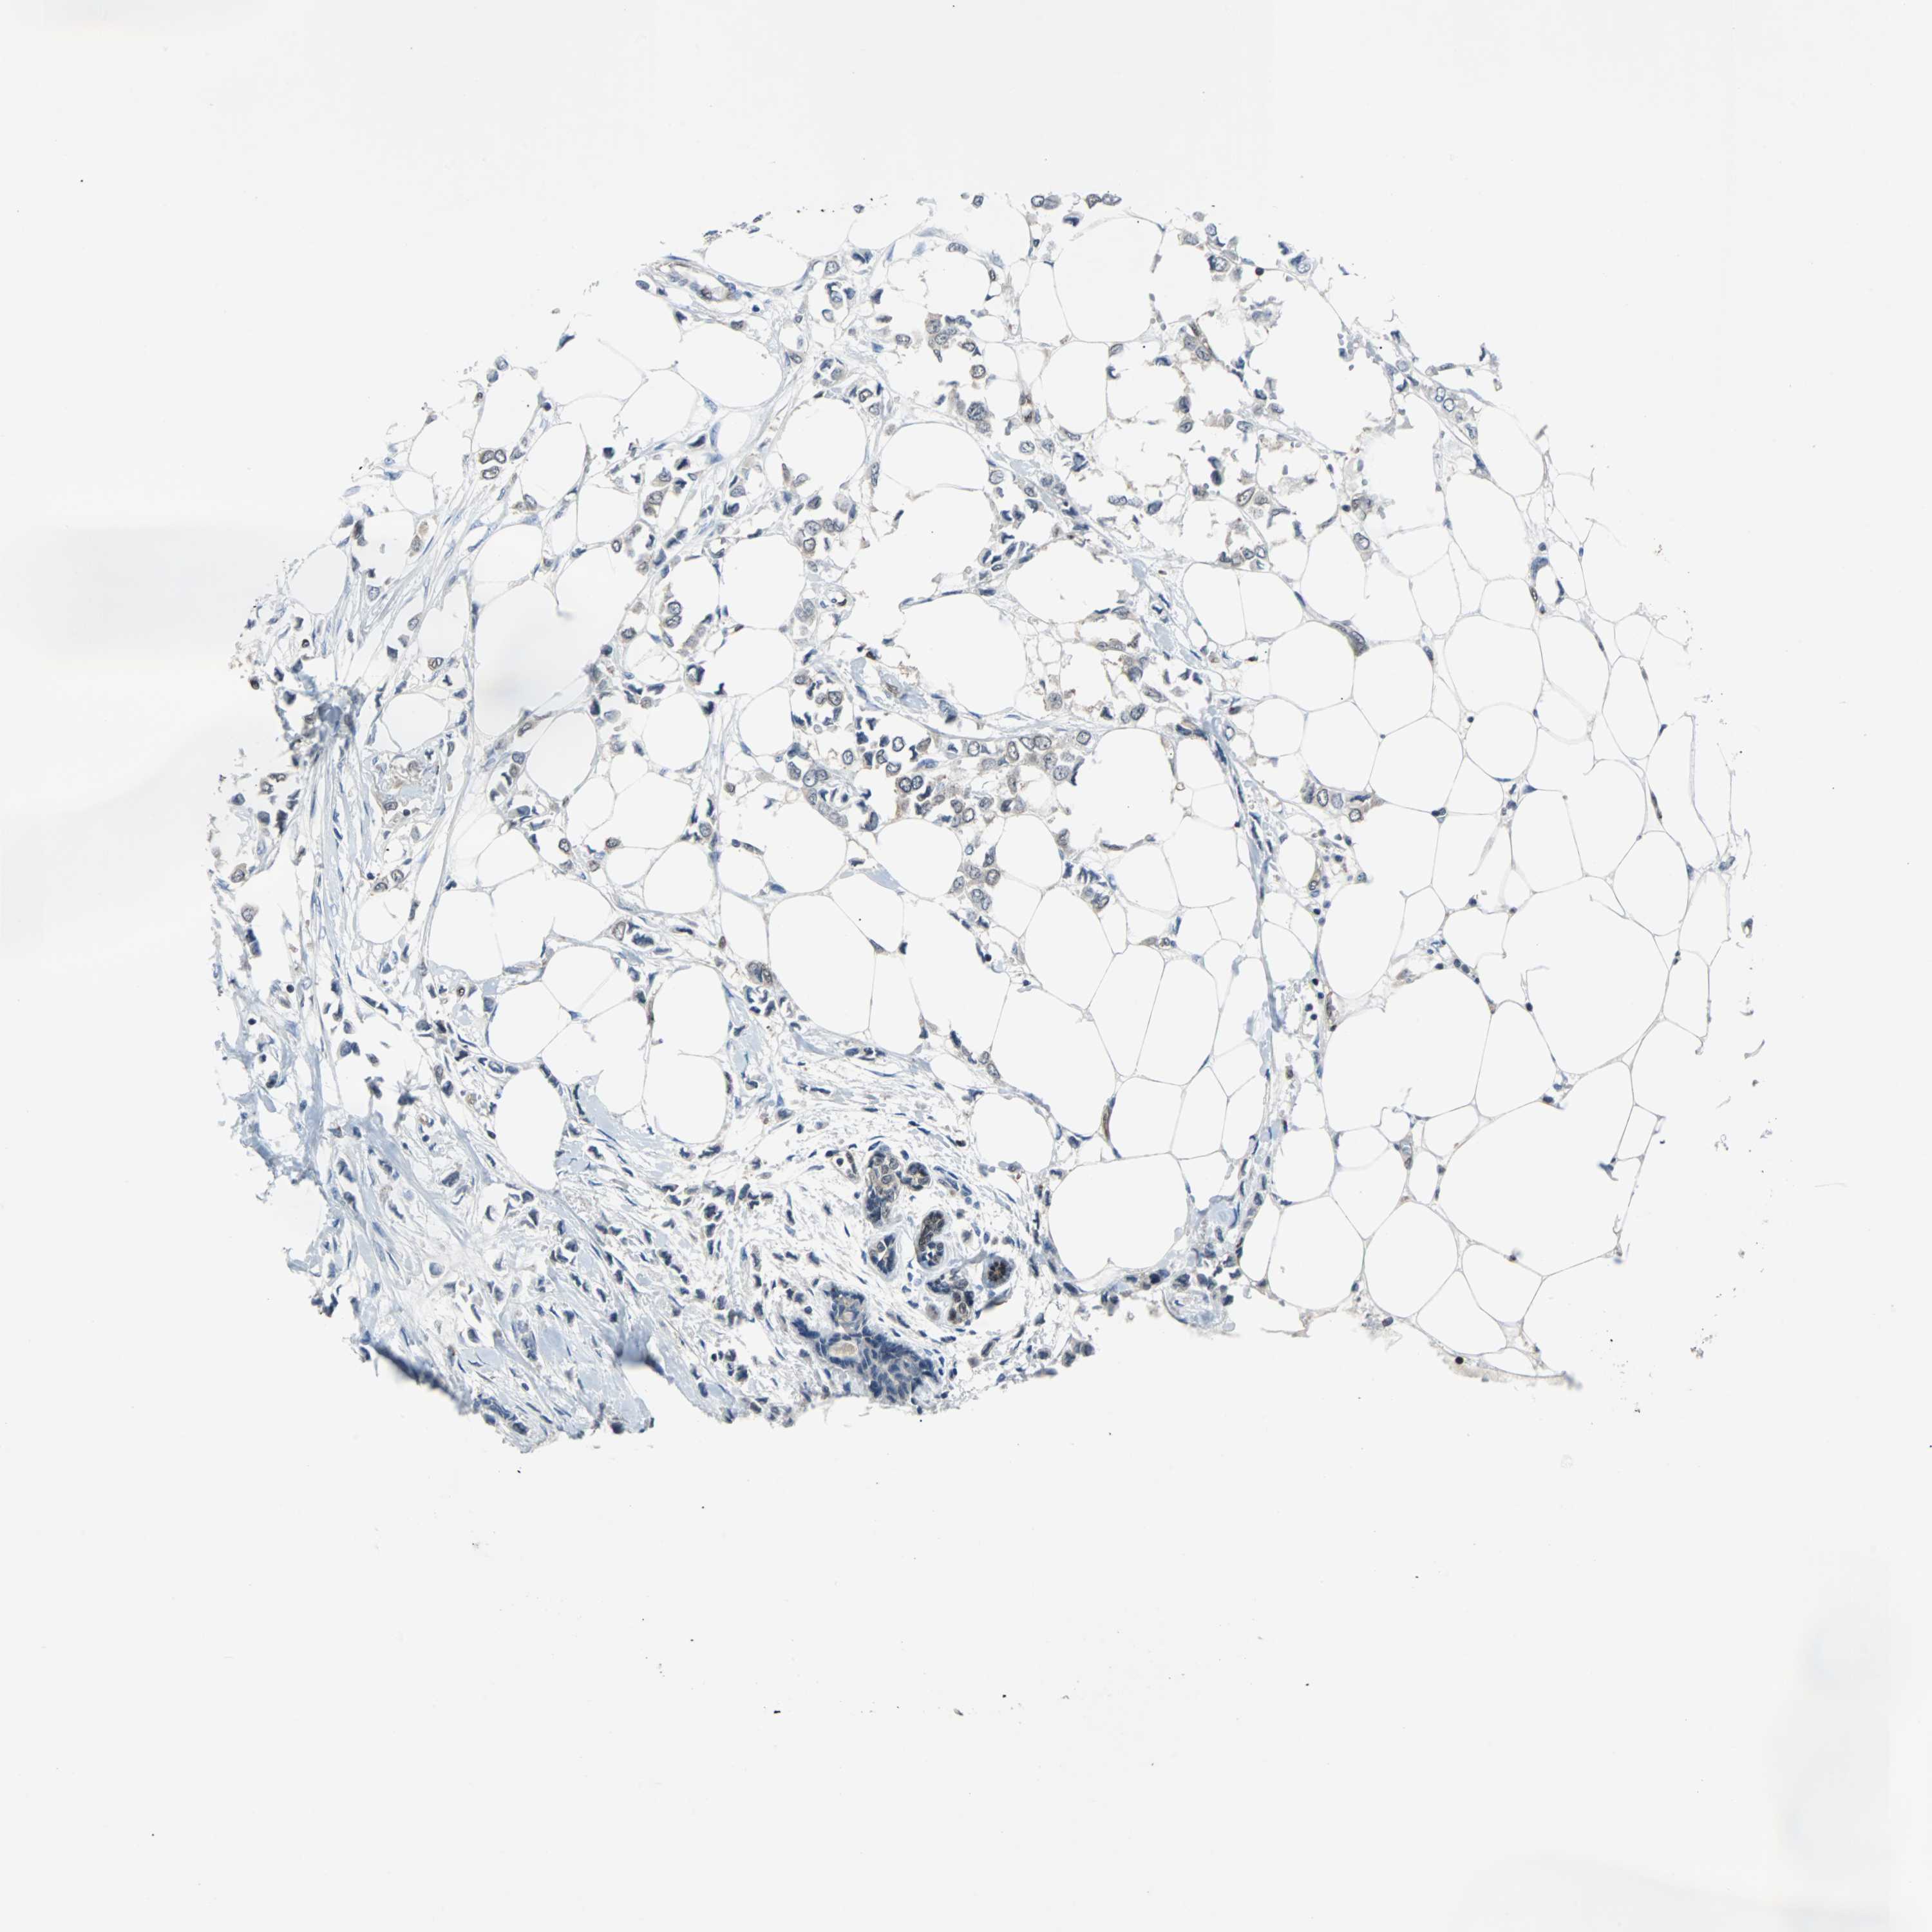

CANCER BREAST CANCER Show tissue menu

BRCA TCGA BRCA VALIDATION PROTEIN EXPRESSION